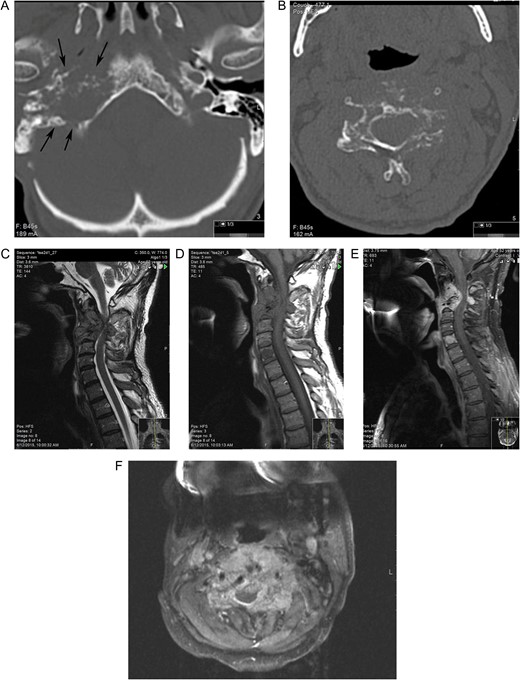

(A) Osteolytic invasion by paraganglioma (B) tumor cells expressing chromogranin A.

Awareness of imaging manifestations of spinal metastatic disease is essential for both the diagnosis and the follow-up. Bone scintigraphy has been the standard initial imaging method for screening of skeletal metastases. CT scans can recognize a bony metastatic lesion earlier than an X-ray. Both bony involvement and neural compression from epidural tumor are demonstrable by MRI, however, MRI cannot distinguish this lesion from other spinal tumors [4, 6]. Thus the diagnosis is confirmed on the histology and immunohistochemical analysis of the intraoperative tissue [4]. In our report, the presence of an infiltrating mass with tumor cells arranged in solid nests, osteolytic invasion, increased number of mitoses and tumor cells positive for chromogranin A confirmed the diagnosis.